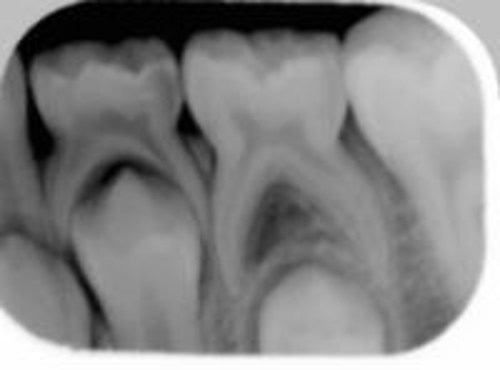

Vi tager røntgenbilleder af tænderne, hvis vi har mistanke om, at tænderne ikke skiftes normalt.

På dette røntgenbillede kan man se de nye tænder, som ligger i kæben neden under mælketænderne.

På første røntgenbillede er den blivende tand ved at skubbe mælketanden ud. På det andet er mælketanden lige ved at falde ud.